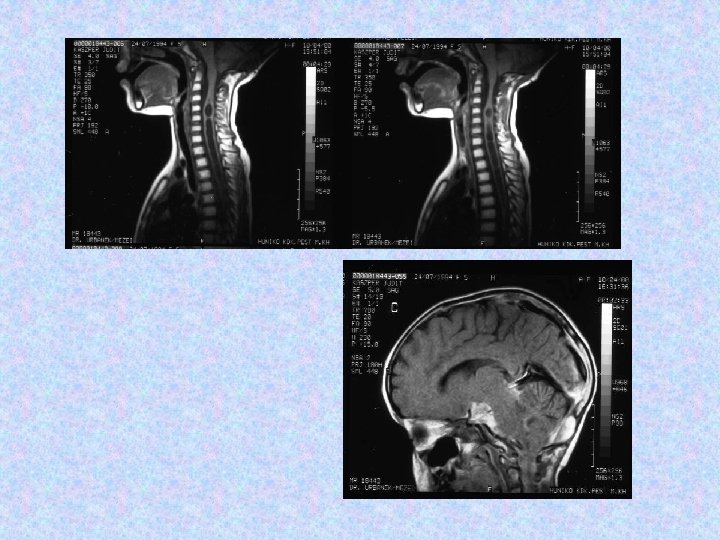

• MR vizsgálat készült liquorpassage zavar miatt. • MR vizsgálat meningeális kontraszthalmozást mutatott a bazális ciszterna, a cerebri media, a ciszterna magna területében. • Felmerült a meningitis basilaris gyanúja, amely nem igazolódott. • Liquor fehérje: 7, 05 g/l, glükóz: 5, 0 mmol/l, sejtszám 10/látótér. Baktérium nem tenyészett ki. Mikrobiológia, szerológia negatív. Citológia gyulladásos szedimentációt véleményezett. Tumor sejtek nem voltak láthatóak. • Spinalis MR thoracalis compressziót, meningeális szóródást mutatott.

• 1998. június 30 -án jobb oldali VP shunt került behelyezésre. Biopsziát későbbre terveztek. • 1998. július 20 -án készült CT beszűkült szupratentoriális kamrarendszert mutat. A shunt jó pozícióban helyezkedik el. • Az 1998. augusztusi MRI nem mutat progressziót sem a kraniális, sem a spinális folyamatokban. • Az 1998. december 7 -i MR felvétel progressziót mutat. Neurológiailag a betegnek kétoldali Babinski tünetei, élénk mélyízületi reflexei vannak, izomzata hypotoniás. Egyebekben negatív státusz. A shunt közepes nyomás mellett jól vezet.